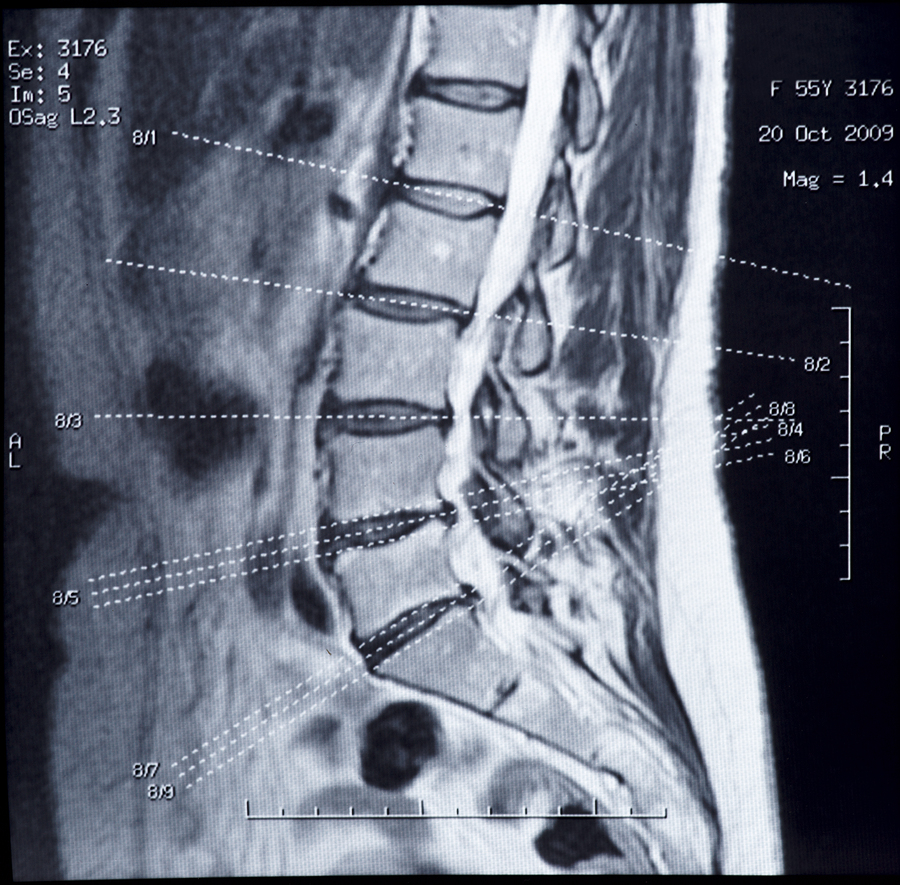

When reviewing an MRI report, he recommended adjusters be on the lookout for:

- Hypertrophy which is swelling of tissue caused by pain, not trauma.

- Desiccation, the drying out of discs, typically reduces their flexibility and height.

- Osteophytes, also known as bone spurs.

- Narrowing of the foramen, where nerve roots don’t have enough room to pass through the foramen.

According to Wertz, the first three have nothing to do with trauma and are typically due to degenerative changes.

As far as experts, Wertz recommended using a forensic radiologist. This type of specialist can determine evidence of acute trauma, swelling or bruising, and whether a fracture was recent or long term. They can also measure disc bulge size.

According to Wertz, adjusters should pay particular attention to claims involving lumbar disks. That’s because they don’t move much. Science says a speed above 21 miles per hour is needed for the likelihood of a disc herniation. If a claimant alleges damaged discs due to a low impact crash, adjusters need to consider whether the impact could have exacerbated a pre-existing injury.

He also said that current textbooks state that herniated disks are unlikely unless massive bone injuries were also sustained.